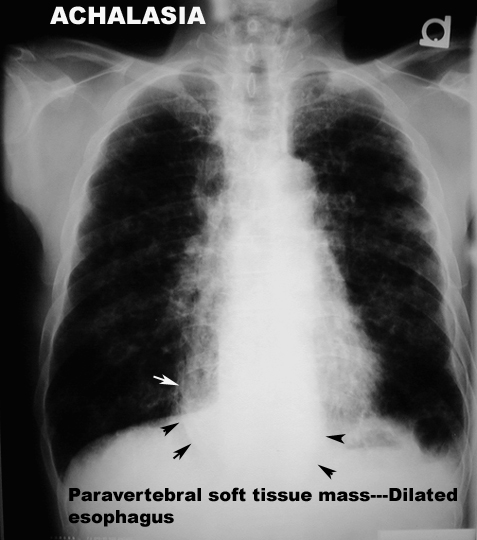

GI and Abdomen Case 1: Achalasia

Degeneration of myenteric plexus in the region of

gastro esophageal junction causes absence of relaxation. This progresses to massive proximal dilatation of the esophagus.

Radiological Features:

- Massive dilatation of the esophagus with air fluid level

- Aspiration - infiltrative changes both lungs